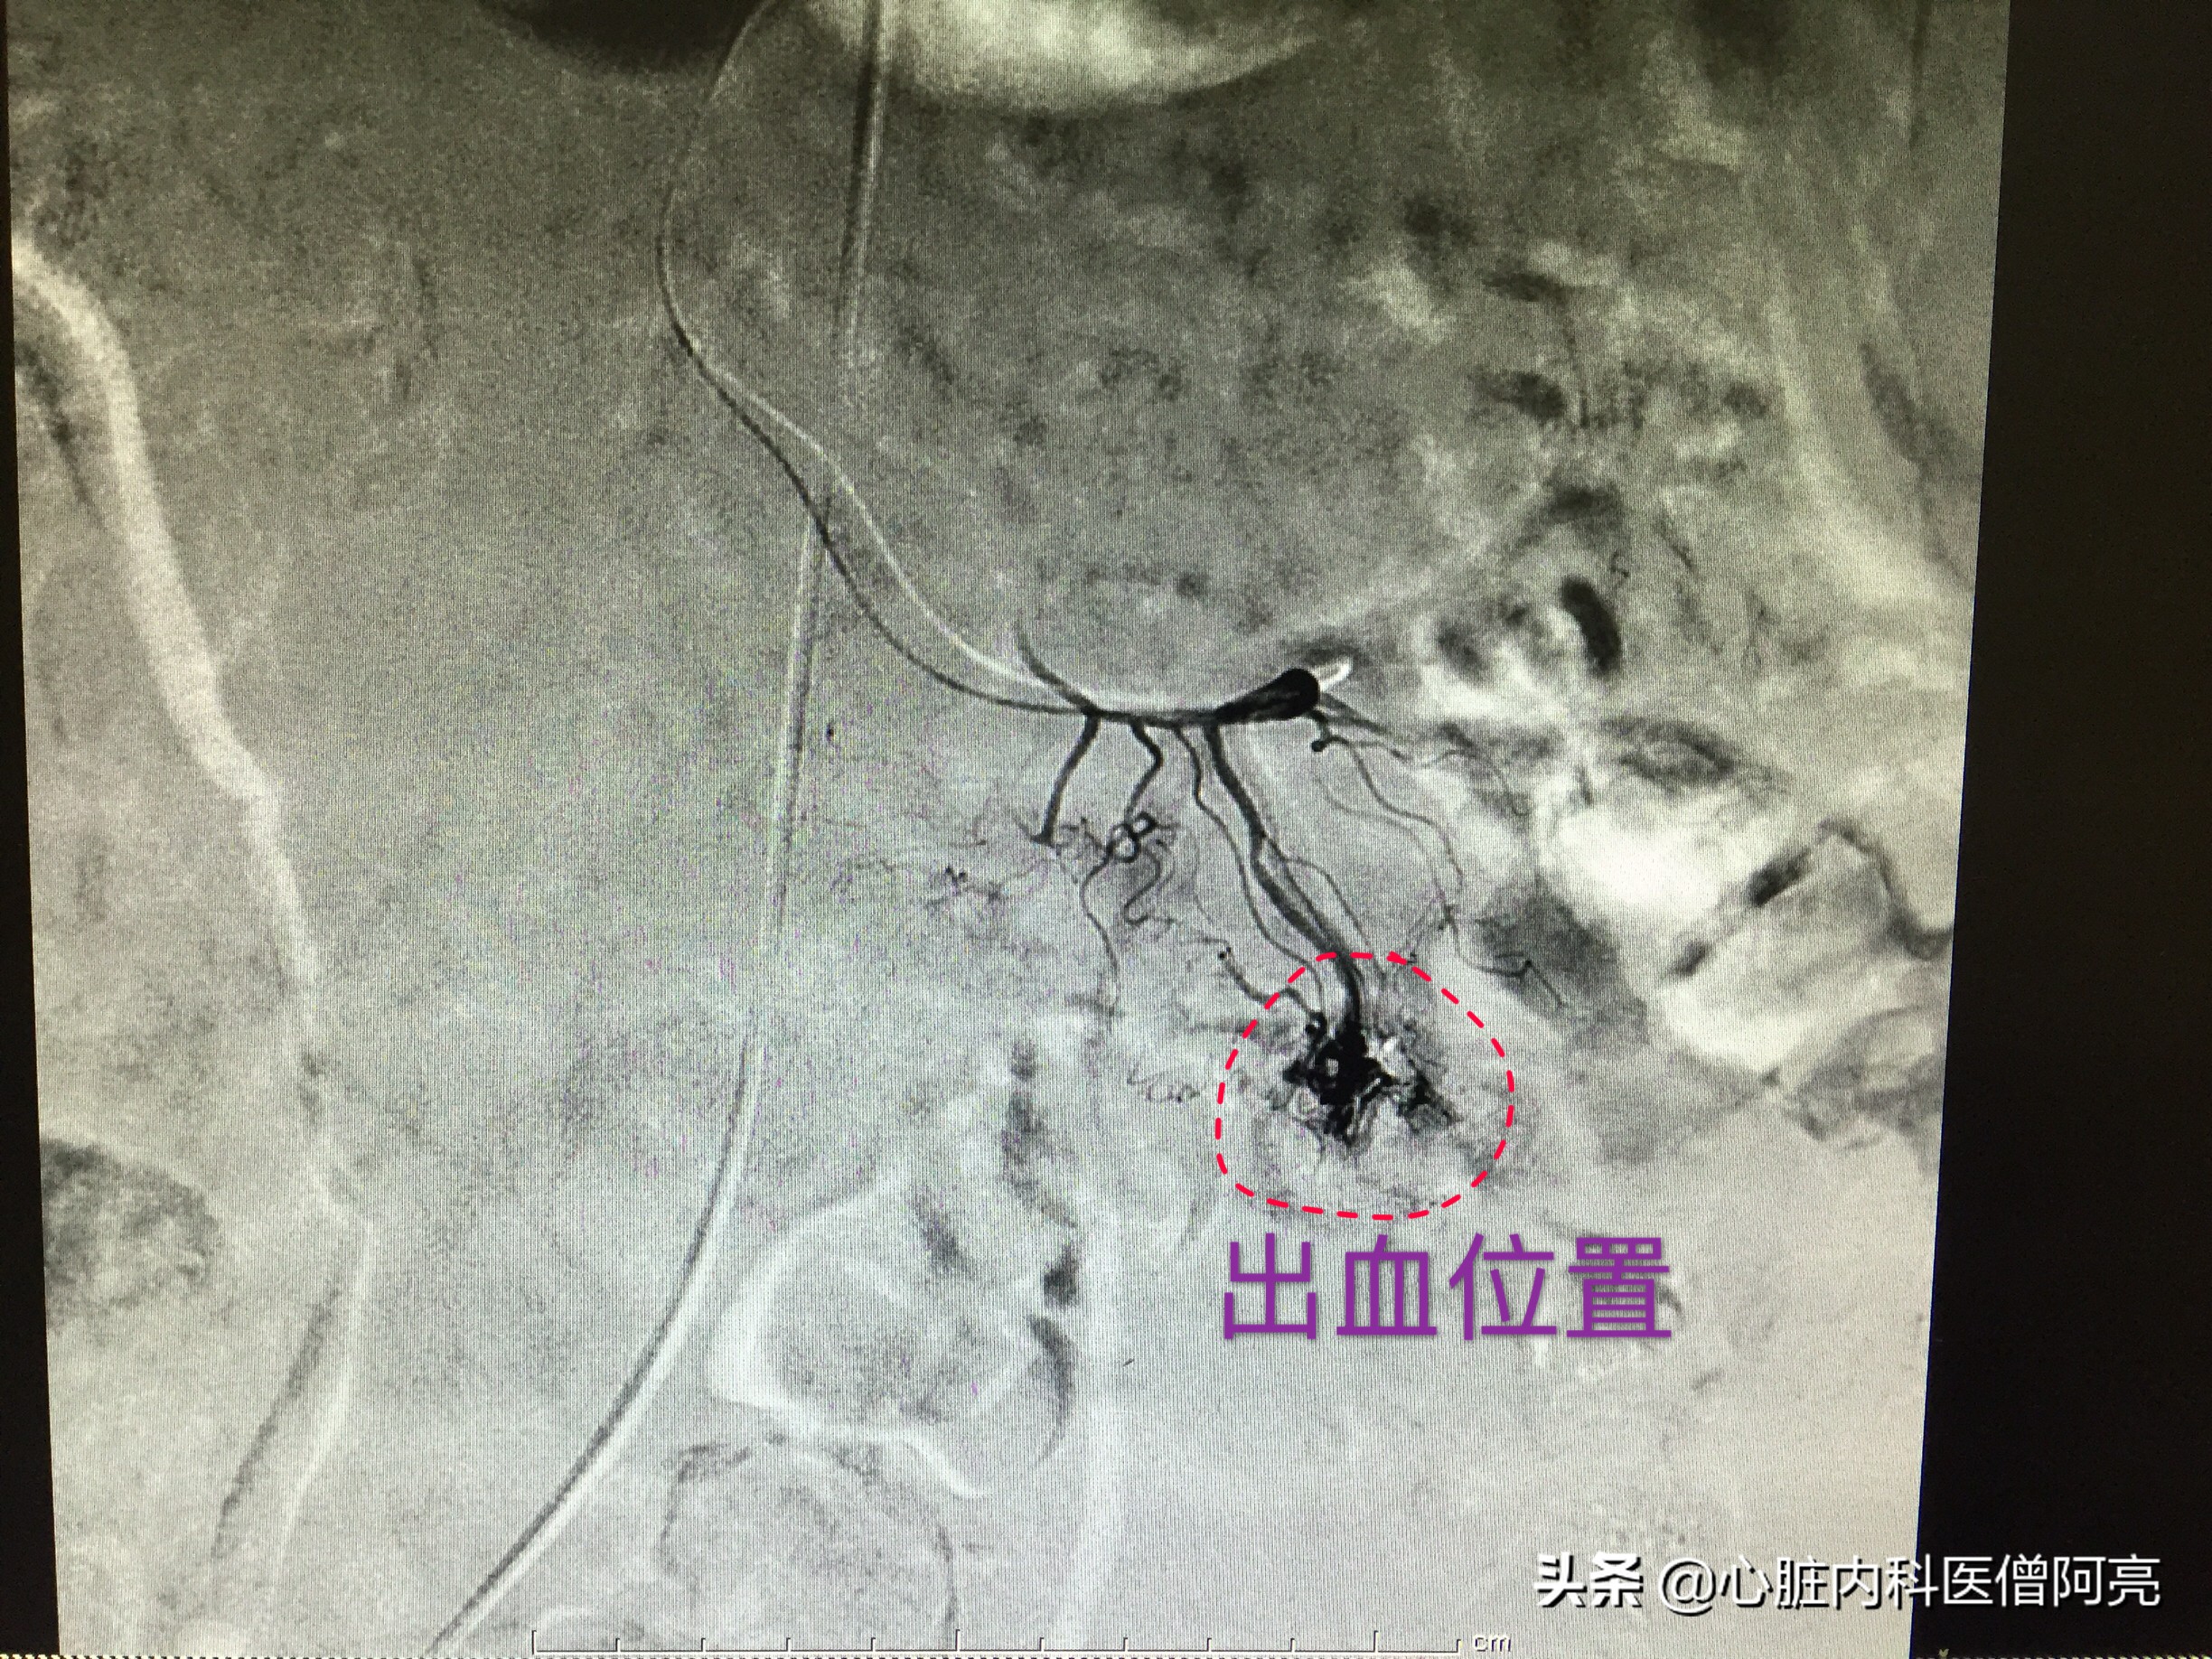

感谢我院的放射介入科同事的倾力相助,造影还是发现了给空肠供血的一个动静脉畸形!并顺利用弹簧圈做了封堵。

胃肠道血管造影发现动静脉畸形